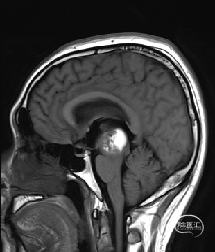

5.术后72小时复查磁共振提示海绵状血管瘤全切。

术后72hMRI复查